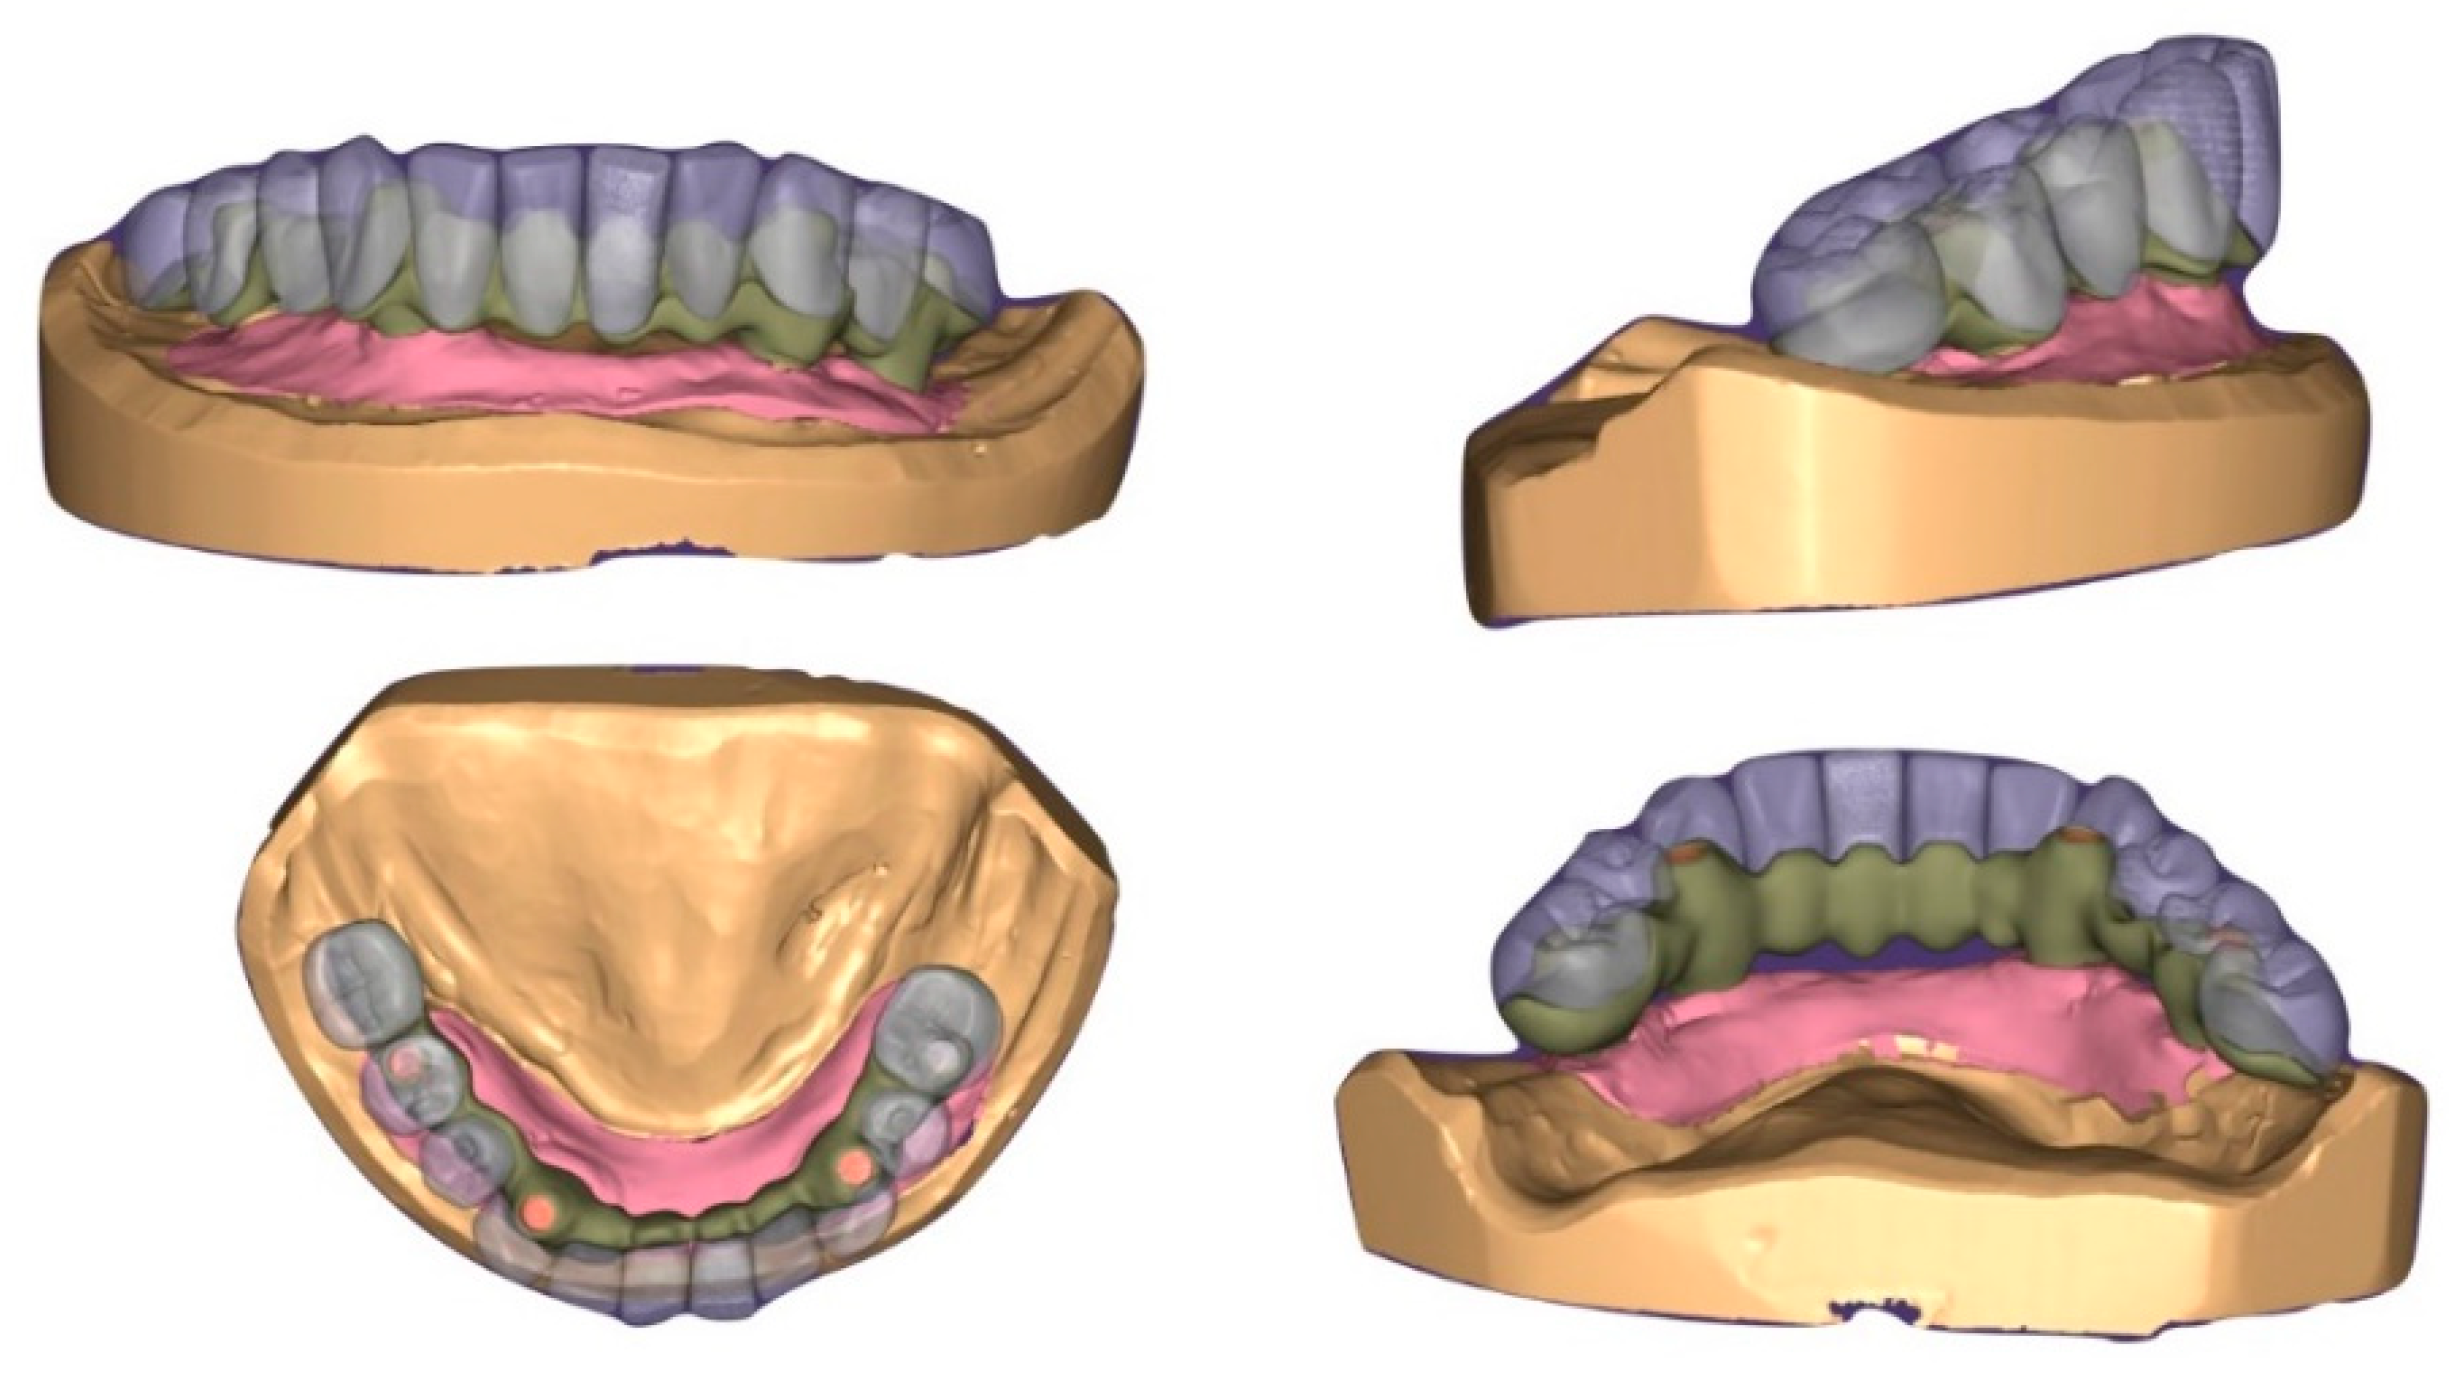

4. Results